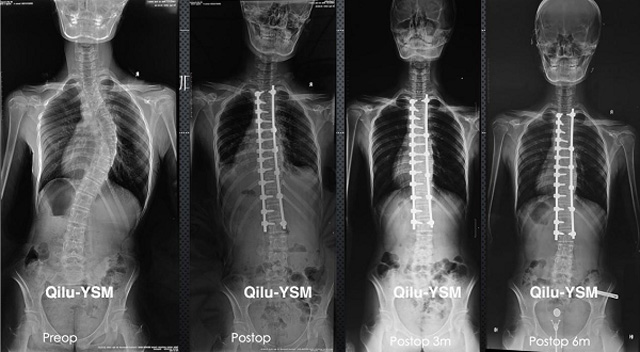

懸吊DR-全電動型機架DR檢查主要用于胸部、四肢、關節(jié)、脊柱等,主要檢查肺部炎癥、腫瘤、結核病、四肢骨關節(jié)的骨折、四肢關節(jié)、脊柱外傷等。DR就是X光,是一種數(shù)碼影像,曝光時間很短,攝像量很小,影像質(zhì)量也很好,可以說是一種替代CR的方法。DR檢查有其局限性,需要做CT平掃等檢查,周圍淋巴結的轉(zhuǎn)移以確定病變的良惡性、范圍、大小、與鄰近組織的關系。